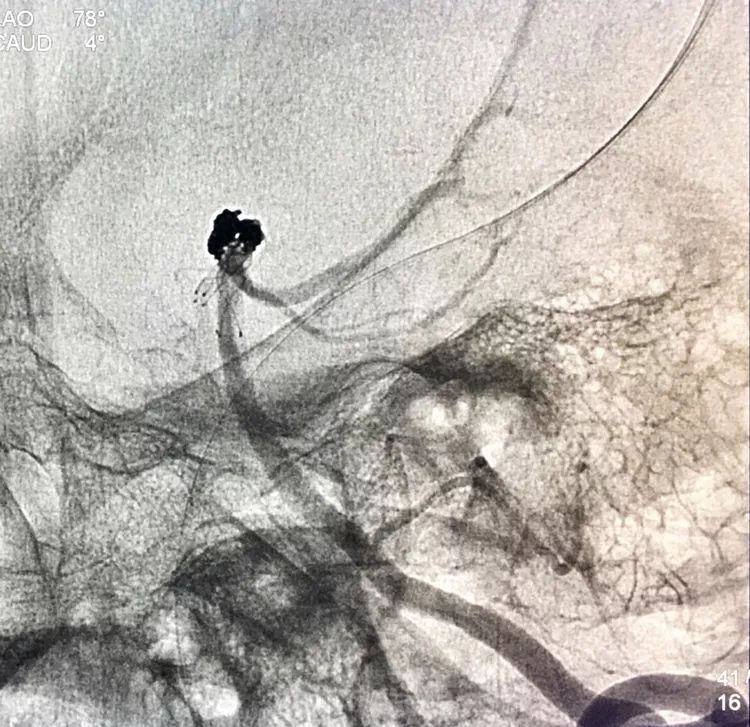

2.17.5.27 DSA+栓塞

左椎动脉正位造影可以看到指向左方的子瘤。

左椎动脉工作位路图

Sychro14微导丝携Headway21支架导管经左椎动脉-基底动脉进入右侧PCA,因瘤颈主要累及右侧PCA,故计划支架跨基底动脉顶端动脉瘤释放于右侧PCA-基底动脉内。

将LVIS支架(3.5×15)跨瘤颈释放于右侧PCA-基底动脉内

此时从工作位(右斜17°反汤9°)看弹簧圈分布致密,微导管头已被顶到瘤颈处

工作位造影看动脉瘤栓塞满意,子瘤已不显影,是不是可以收手了呢?

回到工作位造影,显示基底动脉顶端动脉瘤完全栓塞,基底动脉顶端四根血管畅通。

术后左椎动脉正位、侧位的造影和蒙片